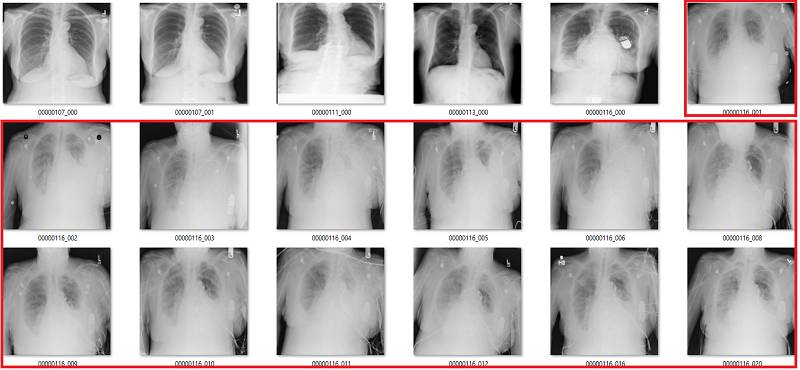

这部分要说该数据集中基于标签的图像。它们是随机选取包含 18 张图像的序列集,并非精挑细选。

我尽量保持谨慎,当一个案例模棱两可的时候,我选择标出标签类别。在所有图像中,红色 = 明显错误的标签;橙色 = 怀疑态度,我没有指出这个问题,但是不能排除这种怀疑。(出于临床诊断的习惯 :p)

渗出(Effusion)

在该案例中,蓝色的标签表示它们存在显著性的肺部疾病。

渗出(effusion)表示在肺部周围空间有积液。造成该病变的原因非常多,但主要原因分为由胸膜和肺部疾病引起的积液。

我并不清楚什么确定或代表了显著性肺部疾病中有积液存在。在很多情况下,甚至直观地识别这些积液都是不可能的,只不过我们知道积液会存在,所以我们也就这样描述它了。上图最后三个肺部影像就是一个非常好的例子,在我看来,这些病例的主要病理还是固结(consolidation)。

我可以看到识别较小和分离的胸腔积液的价值。上图中约有 6 张影像是这样的情况,包括第一张和第三张。没有肺部疾病来表明积液的成因,这令标签「积液」越发突兀。

我还可以看到识别较大积液的好处,它们可能需要我们的介入进行治疗,如使用器械将它们排出。第 10 张图就正好是这样的案例。所以其实我并不太了解标签的含义,因为不是基于临床实践的指导思想并不是很有用。